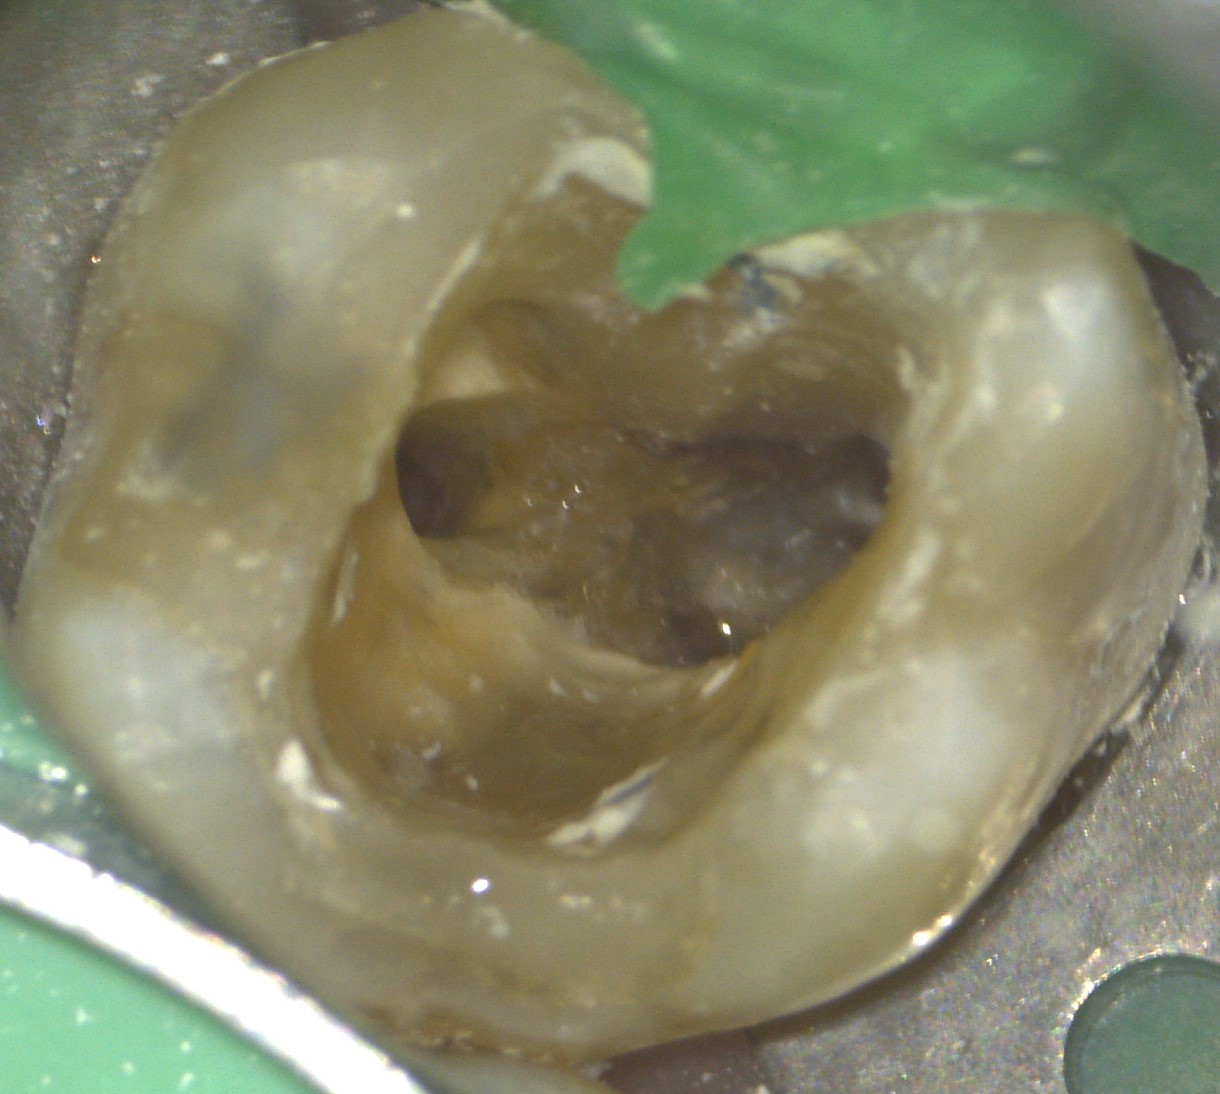

Raicov博士徕卡显微镜使我确信我所做的处理是正确的。对于假体工作,我可以检查准备的准确性。我发现显微镜也是一个非常有用的诊断工具。以敏感牙为例,在原因难以确定的情况下,优秀的显微镜光学和光显示裂缝,或我们在根管治疗中发现了侧管。这是完全不同的诊断,当然每一种都需要不同的治疗。

Raicov博士:我的一些病人是由其他同事推荐的,所以我们使用优秀的记录设备来讨论治疗计划。除此之外,照片和视频帮助我向我的病人解释出了什么问题,他们需要什么治疗。如果人们看到图像,就更容易理解发生了什么。我们在每一个牙髓治疗过程中拍摄照片,并使用它们为内部文件的目的,太。